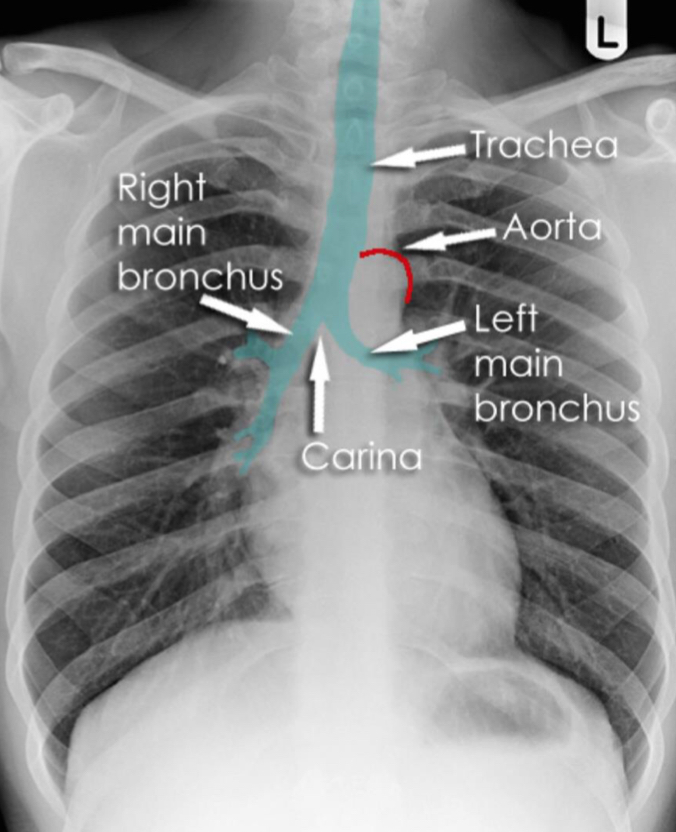

What should you see on a chest x-ray when assessing the trachea?

Left hilar point should always be higher than right, if altered then pathology

Atrial enlargement carina splays

What contours should you see at the mediastinum, e.g aortic knuckle?

Aortic window and LPA disappear with enlarged lymph node